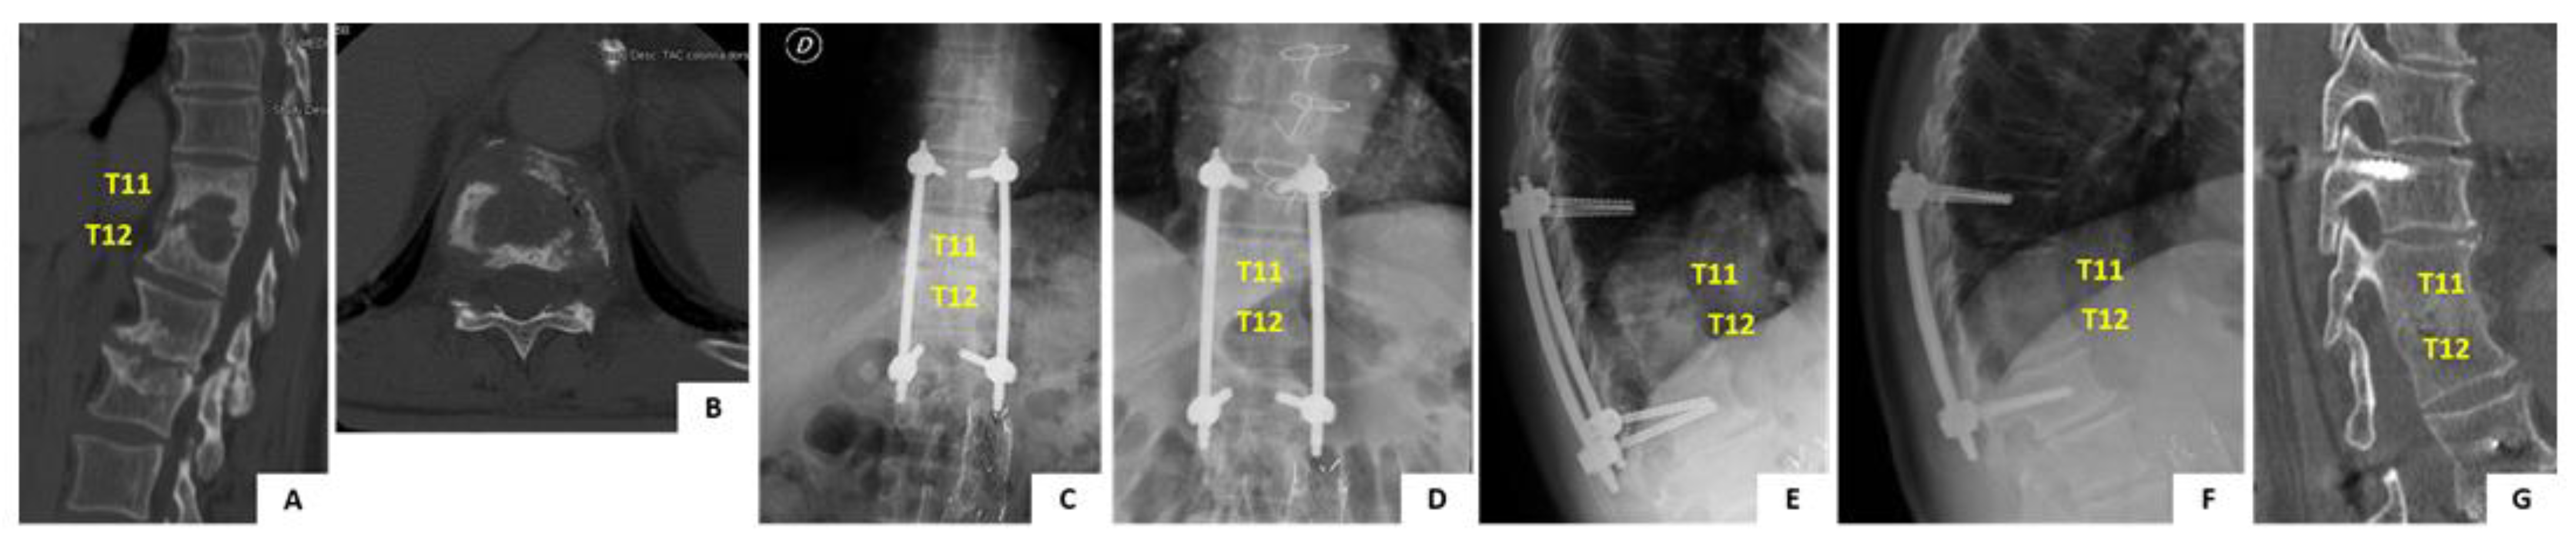

Case Report

In June 2009, a 68-year old man presented to you hospital with a 1 month history of worsening axial back pain at the thoracolumbar junction. Past medical history of the patient was positive for high blood pressure and benign prostatic hyperplasia. At first the patient was assessed by his general practictioner and was prescribed oral antibiotic therapy with ciprofloxacin for a suspect urinary tract infection. Therapy was unsuccessful and patient developed fever, night sweats and fatigue over the course of the following 15 days. The patient was admitted to our hospital with the suspect diagnosis of pyogenic spondylodiscitis. Spinal X-ray, CT and MRI scans were obtained (Figure 5A,B). Imaging showed destructive lesion at T11-T12 with disc and endplate involvement, suggestive of pyogenic spondylodiscitis type B3.1 [11]. A CT guided biopsy of the lesion was positive for S. hominis pyogenic infection. The patient was started on intravenous teicoplanin and ceftriaxone therapy which was continued for 4 weeks and followed by other 4 weeks of iv therapy with teicoplanin and co-trimoxazole. At the end of iv antibiotic therapy the patient was prescribed oral therapy with co-trimoxazole and rifampicin for 4 more weeks. Before starting antibiotic therapy the patient was prescribed a rigid TLSO brace to relieve pain and prevent development of spinal deformity. The brace was poorly tolerated by the patient and for this reason operative treatment with percutaneous posterior screw-rod instrumentation was offered. Posterior fixation from T10 to L1 was performed uneventfully (Figure 5C,E). The patient was allowed free mobilization soon after surgery. Clinical and laboratory parameters improved significantly over the course of the follow-up and complete healing of the infection was determined at 3 months after the diagnosis. The patient is currently 80-years old and completed the 10-years follow-up after the procedure. He lives indepedently at home, does not complain of any back pain. The imaging obtained at 10 years follow-up shows complete healing of the lesion with fusion of the vertebral bodies. No mobilization of the instrumentation is noted (Figure 5D,F).

Figure 5. Pre- and post-operative imaging of the case report detailed in the manuscript. Panels (A,B) show sagittal and axial CT scan imaging of the T11–T12 infected level. Panels (C,D) show comparison of standing AP X-ray imaging of the spine immediately after surgery and at 10 years follow-up. Instrumentation is noted with pedicle screws and rods. The instrumentation is bridging the infected level. Panels (EG) show comparison of standing lateral view X-ray imaging of the spine immediately after surgery and at 10 years follow-up. No mobilization of the instrumentarion is noted, the infected level is completely fused and segmental kyphosis is preserved.